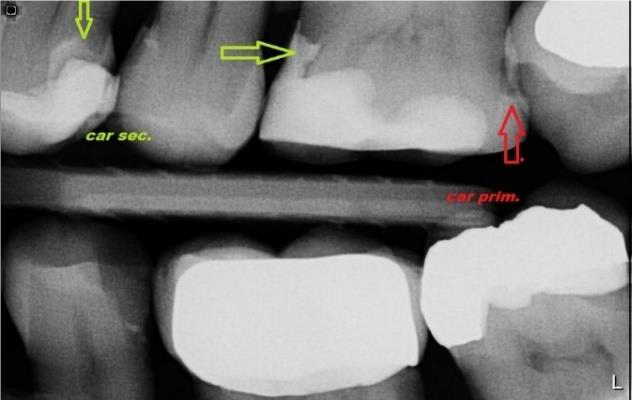

Nový pacient je nejprve objednán na vstupní vyšetření. Během první prohlídky vyšetříme stav Vaší dutiny ústní, zubů a parodontu. Při vyšetření jsou zhotoveny RTG snímky. Nejčastěji zobrazovaným patologickým jevem v ordinaci zubního lékaře je zubní kaz. Včasná diagnostika je zásadní pro rozšíření kazu a následnou sanaci. Odhalení demineralizované skloviny v aproximálních prostorech je především v začátku kazivého procesu možné pouze pomocí rtg snímku. Rovněž sekundární kazy jsou bez snímku většinou nerozpoznatelné. Zubní kaz se na diagnostickém snímku jeví jako tmavší stín právě kvůli demineralizaci zubní tkáně.